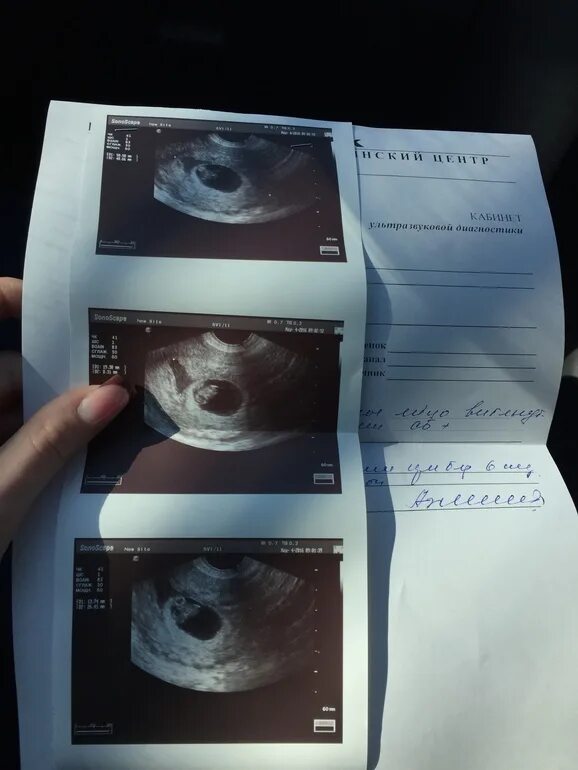

Узи 6 месяцев